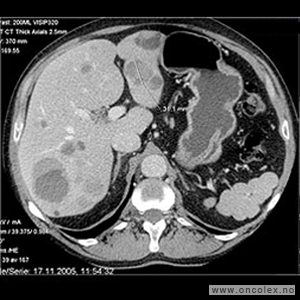

Bildeeksempler